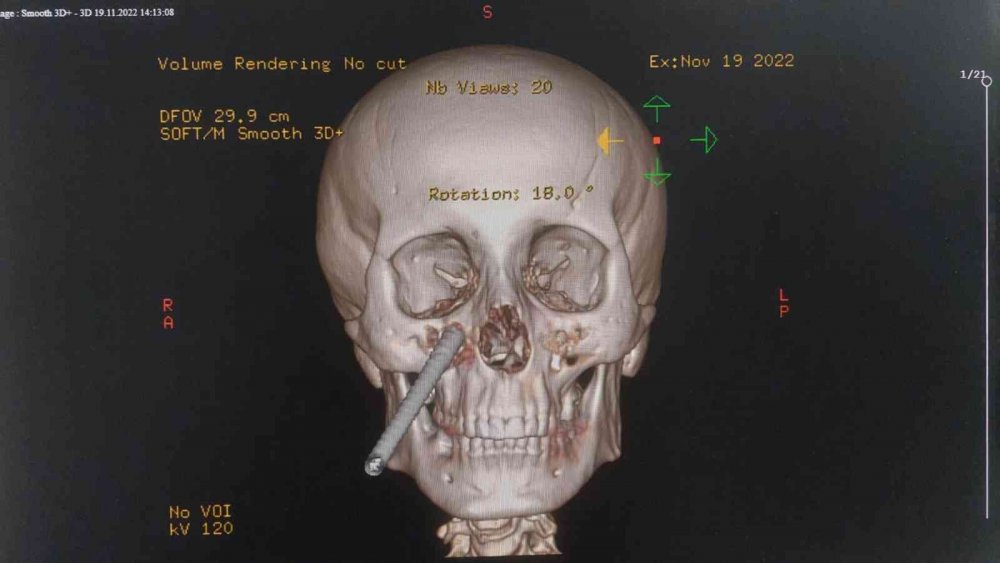

Yüzüne saplanan demirle hastaneye kaldırıldı

Edinilen bilgiye göre, Giresun'da çalıştığı inşaatta demirin üzerine düşen Celal Sayar'ın (39) yüzüne inşaat demiri saplandı. Yüzünde demir saplı halde Giresun'daki hastaneye kaldırılan Sayar, ilk müdahalesinin ardından demirin yüzünden çıkartılması için Samsun'a sevk edildi. Celal Sayar, Samsun Eğitim ve Araştırma Hastanesinde ameliyata alındı. Yüzündeki demir çıkartılan Sayar, daha sonra hastanenin yoğun bakım servisinde tedavi altına alındı.